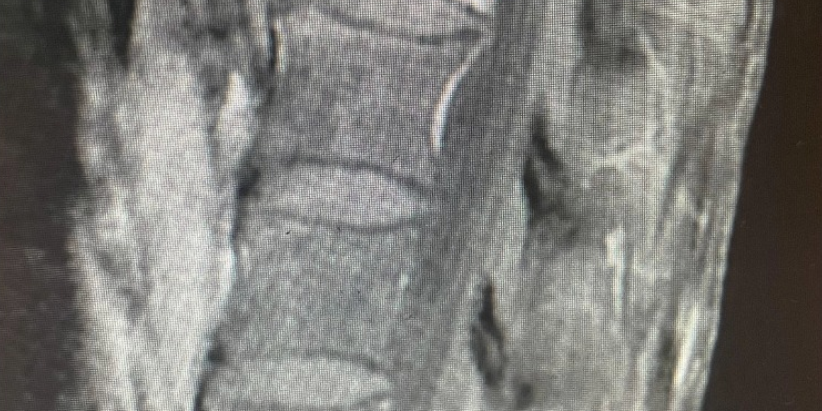

She presented with back pain and Leiomyosarcoma which had spread to the L1 vertebral body. Radiation treatments and cement injection to L1 were tried by the oncologists but her vertebrae collapsed anyway. The first 2 MRI pictures show the progressive collapse.

She was taken to surgery about 4 1/2 years ago and the entire L1 vertebrae and tumor was surgically removed from the front and back with the help of a vascular surgeon. I had to place extensive hardware from the front and back to support the missing vertebrae. She recovered well. Recent CT scans showed no further cancer in the spine. (Photos 3-5.)